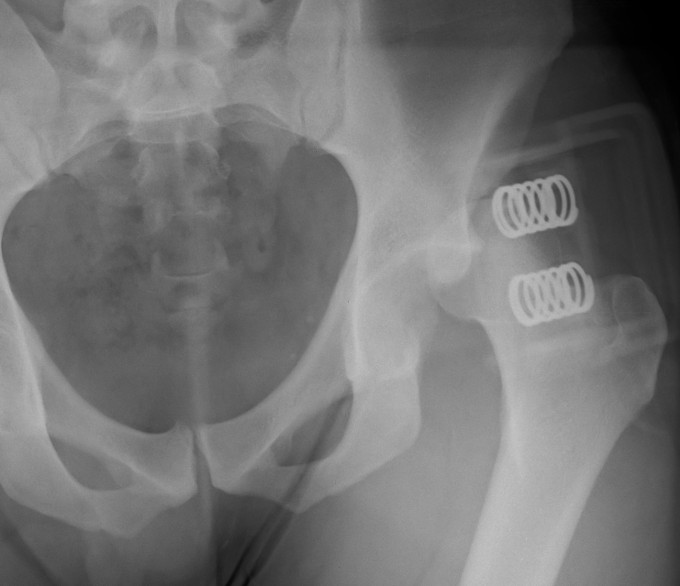

Posterior dislocation

- leg shortened, flexed, adducted & internally rotated

- head small on xray

2. Assess stability

Posterior wall fracture > 40%

- need ORIF for stability

Posterior wall fracture < 40%

- can be unstable

- EUA after reduction to assess stability

- should be able to flex to 90o and some IR without instability

3. Screen for retained fragments

Compulsory CT

- xray will not detect fragments < 2mm

Remove / ORIF depending on size of fragment and location / Pipkin type

4. Reconstruct acetabulum if unstable or incongruent